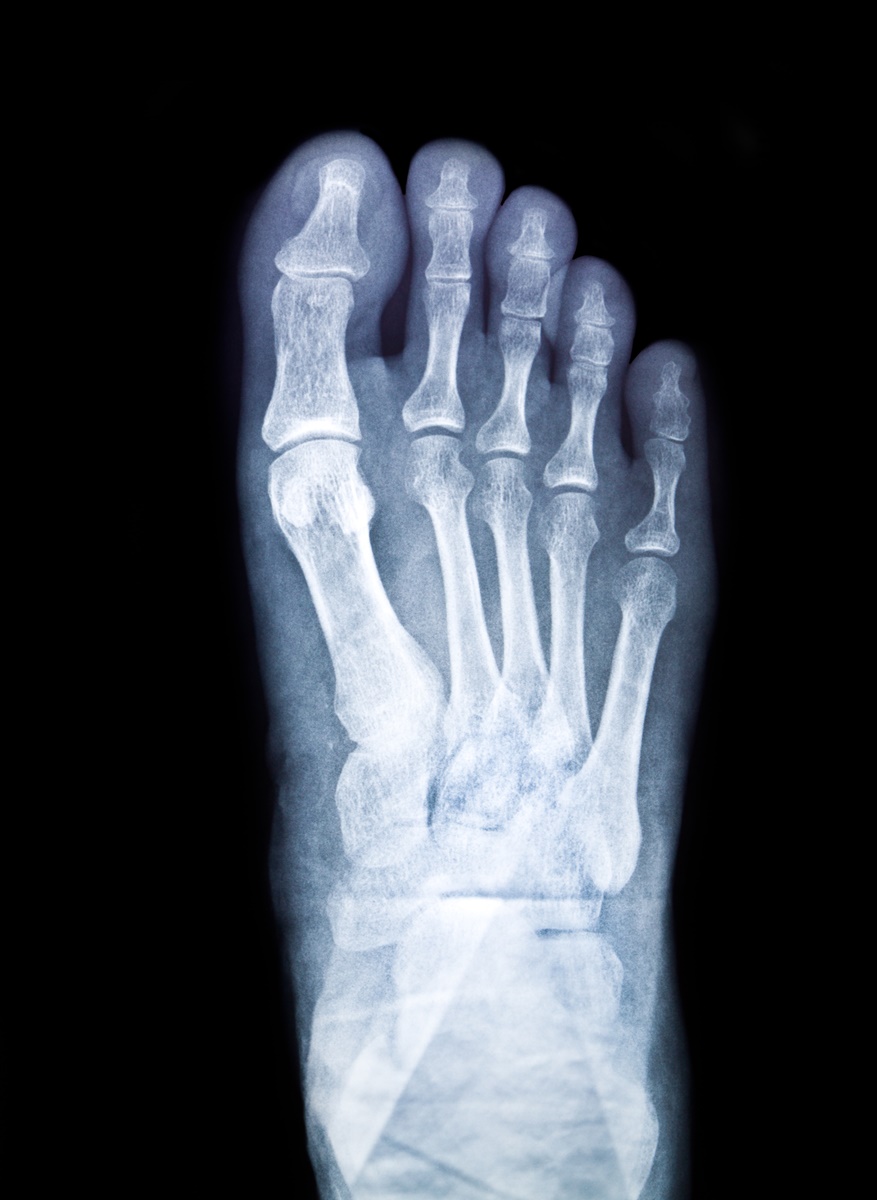

กระดูกงอก คืออะไร?

รศ.นพ.บวรฤทธิ์ จักรไพวงศ์ ภาควิชาศัลยศาสตร์ออร์โธปิดิคส์และกายภาพบำบัด คณะแพทยศาสตร์ศิริราชพยาบาล มหาวิทยาลัยมหิดล ระบุว่า กระดูกงอก คือกระดูกที่งอกเกินขึ้นมา อาจจะงอกเกินมาตั้งแต่กำหนด สัมพันธ์กับการเป็นคนมีเท้าแบน (ไม่มีอุ้งเท้า) หรืออาจเกิดจากที่เท้าบาดเจ็บจากการใช้งานหนักหรือผิดท่า แล้วกระดูกมีการซ่อมแซมตัวเองที่ไม่ดีนัก โดยกระดูกที่งอกขึ้นมาใหม่อาจเสียดสีกับเส้นเอ็นที่เท้า ทำให้บาดเจ็บได้ และร่างกายอาจจะซ่อมแซมด้วยตัวเองได้ยาก

คนเท้าแบน เสี่ยงกระดูกงอกกว่าคนปกติ

จากสถิติ คนเอเชียรวมถึงคนไทยที่มีเท้าแบนอาจจะเสี่ยงกระดูกงอกราว 1 ใน 4 สาเหตุของเท้าแบนเกิดจากหลายสาเหตุ ทั้งกรรมพันธุ์ รวมถึงการไม่ใส่รองเท้าตอนเด็ก และการเดินเท้าเปล่าในบ้านตลอดเวลา ไม่เหมือนชาวตะวันตกที่ใส่รองเท้าระหว่างเดินอยู่ในบ้าน การใส่รองเท้าจะช่วยพยุงอุ้งเท้าให้โค้งงอตลอดเวลา ไม่เหมือนการเดินด้วยเท้าเปล่า

กระดูกงอก เป็นได้ที่เท้าทั้งสองข้าง

เมื่อคนเท้าแบนมีความเสี่ยงกระดูกงอก หากเท้าข้างหนึ่งพบกระดูกงอก จึงมีโอกาสที่ 90% จะพบกระดูกงอกที่เท้าอีกข้างหนึ่งได้ด้วย แต่ขนาดของกระดูกงอกที่พบอาจเล็กใหญ่ไม่เท่ากัน